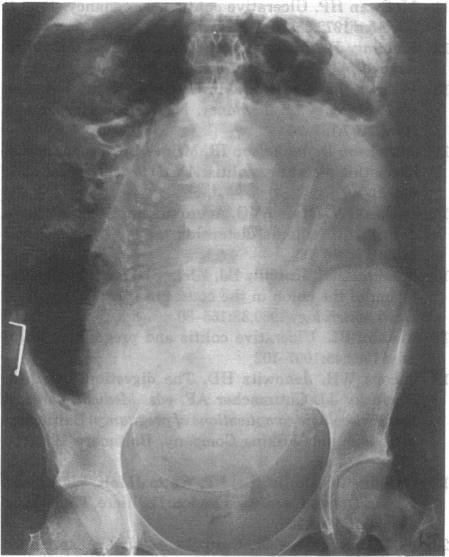

Four patients underwent emergency colectomy during pregnancy or the puerperium for complications of ulcerative proctocolitis. Three had inactive colitis at conception, while in the fourth the disease started during pregnancy. Three patients required subtotal colectomy and ileostomy for toxic dilatation during the third trimester or within 5 days of delivery, and the fourth underwent proctocolectomy postpartum for intractable colitis. There were no maternal deaths but 2 of 4 infants died. One child weighing 1.4 kg survived vaginal delivery during the 33rd week of pregnancy, 2 weeks after his mother had undergone emergency colectomy.

4例患者在孕期或产褥期因溃疡性直肠结肠炎并发症接受了急诊结肠切除术。3例在受孕时患有静止期结肠炎,而第4例在孕期发病。3例患者在孕晚期或分娩后5天内因中毒性巨结肠需要行结肠次全切除术和回肠造口术,第4例产后因顽固性结肠炎接受了全直肠结肠切除术。无孕产妇死亡,但4例婴儿中有2例死亡。1名体重1.4kg的婴儿在其母亲接受急诊结肠切除术后2周,于妊娠第33周经阴道分娩存活。